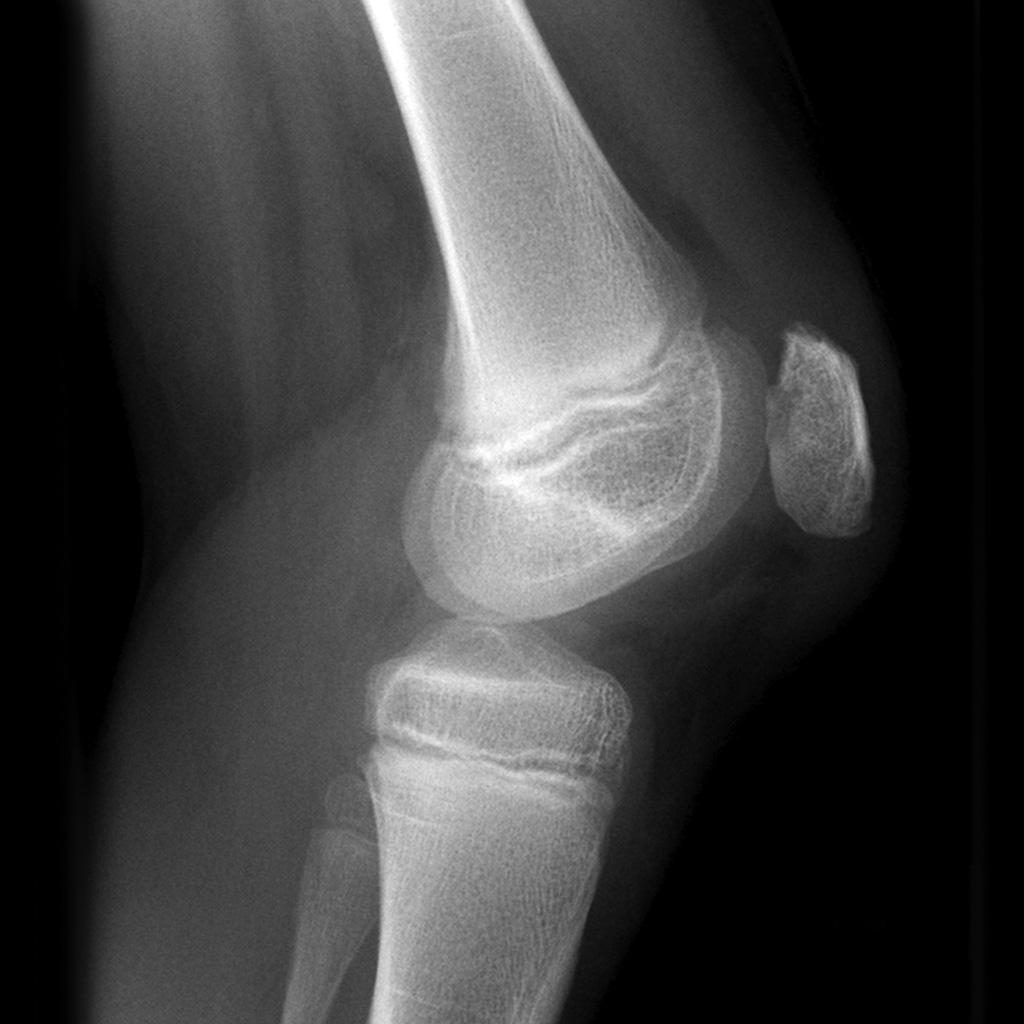

Patellofemoral joint (PFJ) arthritis. A. Skyline XRay showing PFJ Chondromalacia Patella Vs Arthritis Chondromalacia can be an early warning sign of arthritis in the knee joint. If left without treatment, it may develop into. If not effectively treated, these early changes. Patellofemoral arthritis refers to the presence of degenerative changes to the joint. Learn about the most common symptoms of chondromalacia patella, much rarer ones, complications, and. Chondromalacia refers to degenerative changes in. Chondromalacia Patella Vs Arthritis.